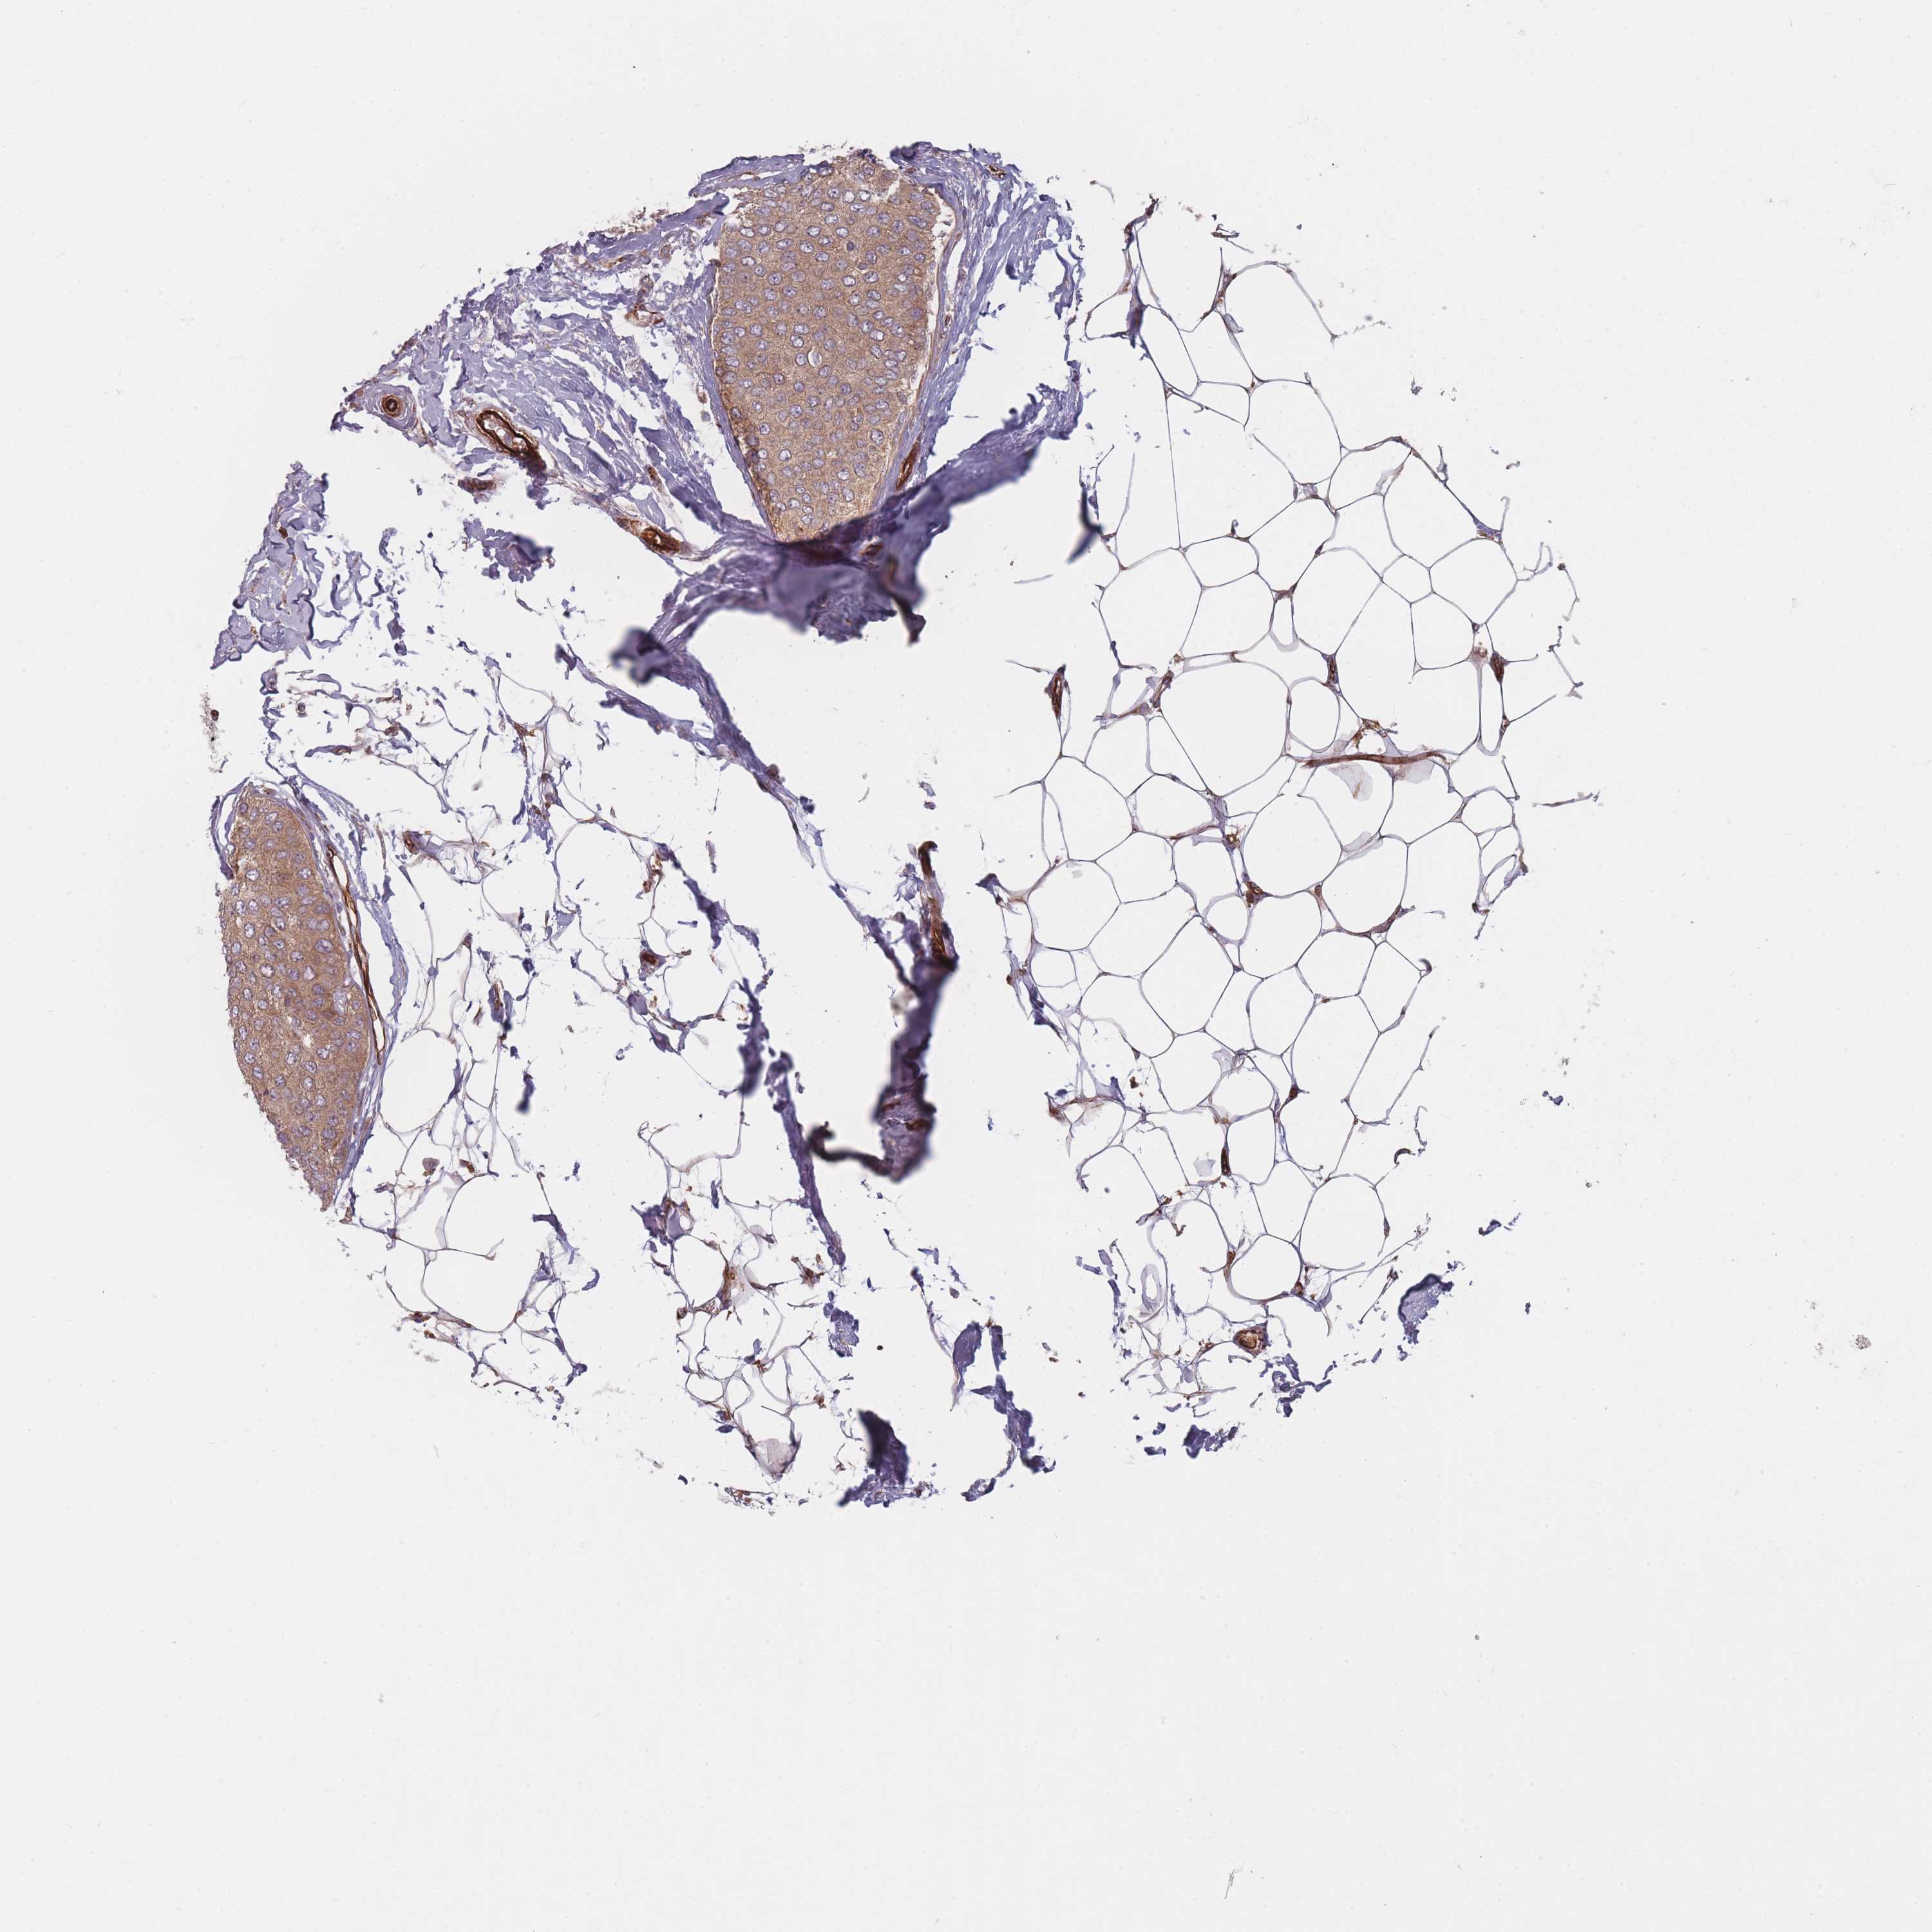

Breast cancer

Human cancer